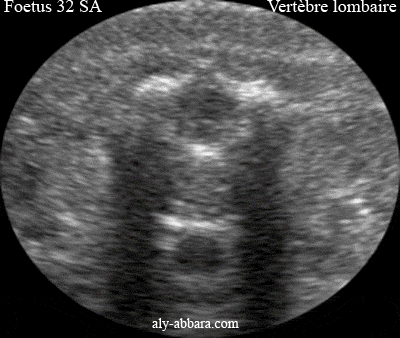

Anatomie d'une vertèbre lombaire chez un foetus de 32 SA

Image échographique montrant les structures anatomiques d'une vertèbre lombaire chez un fœtus de 32 SA

A comparer à une vertèbre thoracique